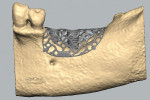

A clinical exam was performed, and a CBCT scan was acquired, which revealed a vertical bone defect in the left posterior mandible (Figure 1 and Figure 2). After the patient accepted a treatment plan involving ridge augmentation and implant placement, the DICOM files from the CBCT scan were sent for the design of a customized titanium mesh (Yxoss CBR®, ReOss) (Figure 3).

Upon approval of the design, the customized mesh was fabricated and delivered to the office for sterilization, and the patient was recalled. An incision was made along the crest of the ridge in the left posterior mandible. Vertical releasing incisions were then made lateral to the retromolar pad and mesial to the cuspid, and a mucoperiosteal flap was reflected to expose the ridge. After the customized mesh was tried in to confirm the fit, particulate autogenous bone was harvested from the mandibular body and ramus using a bone scraper (SafeScraper TWIST, Geistlich Pharma North America). The particulate autograft was mixed with a cancellous bovine bone mineral substitute (Bio-Oss®, Geistlich Pharma North America) and PRF to create a graft mixture, which was then loaded into the customized mesh (Figure 4). Once the mesh was filled with graft material, it was placed over the ridge and secured with two buccal fixation screws (Figure 5). The mesh was then covered with a resorbable collagen membrane (Bio-Gide®, Geistlich Pharma North America) as well as PRF membranes (Figure 6), and the flap was advanced to achieve tension-free primary closure using a horizontal mattress suture technique.